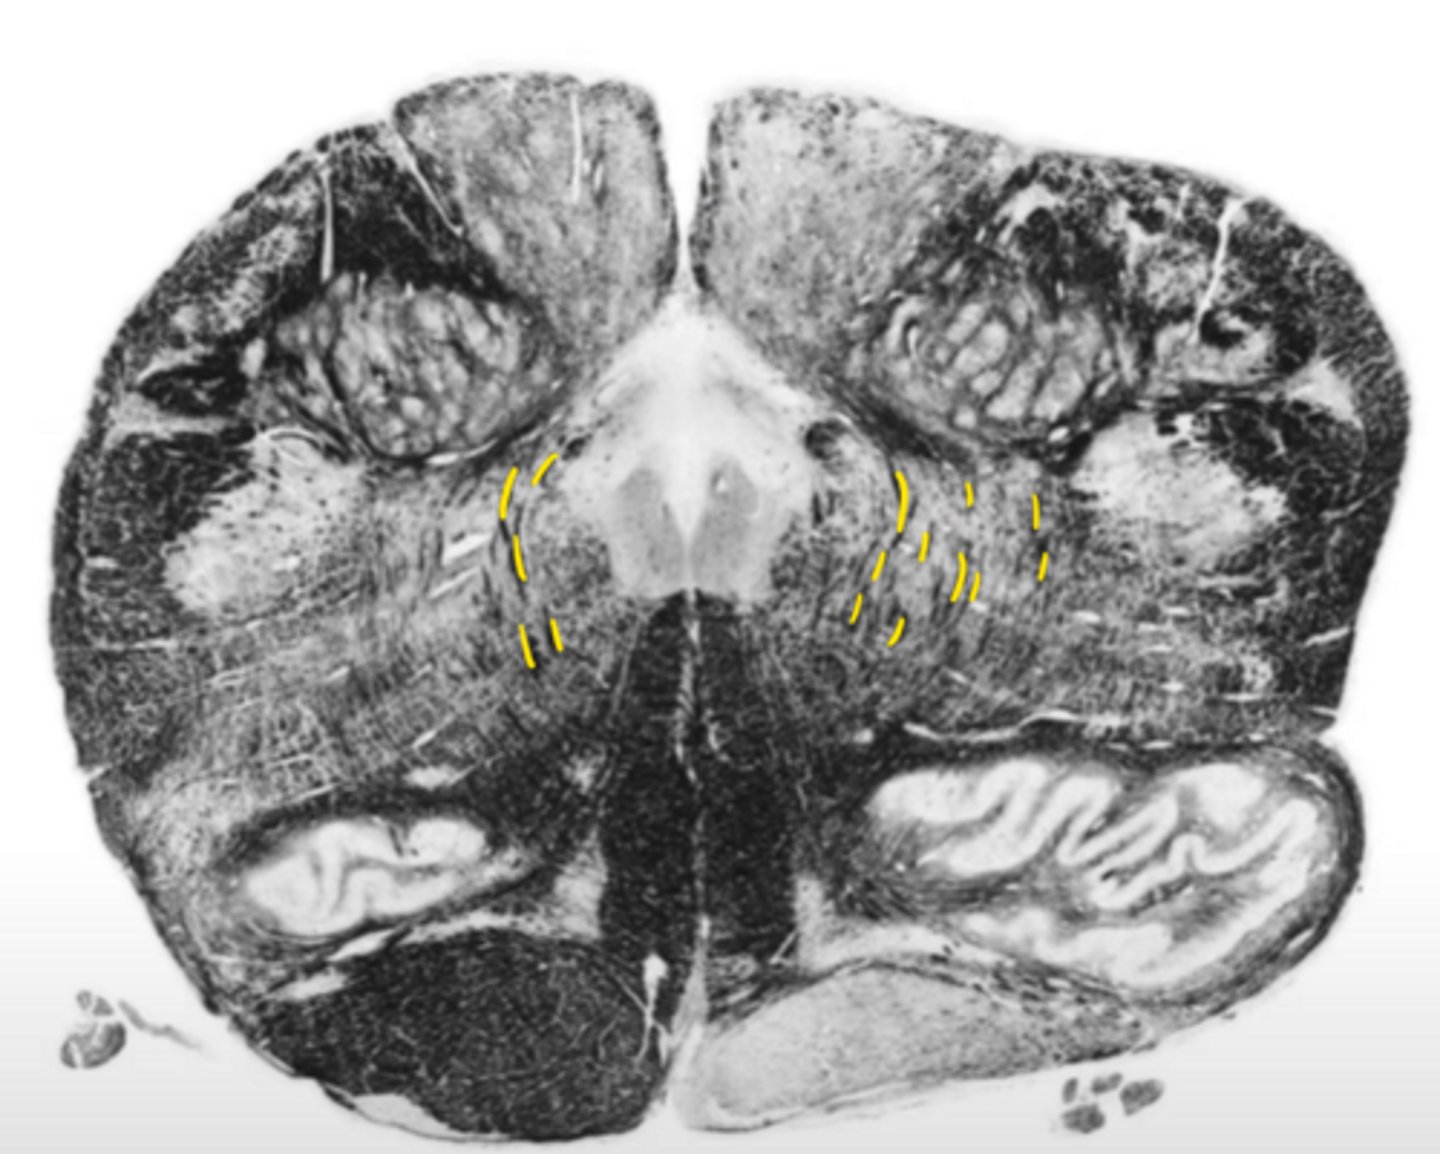

medial lemniscus

ID the structure

vestibular nucleus

ID the nucleus

fourth ventricle

ID the space